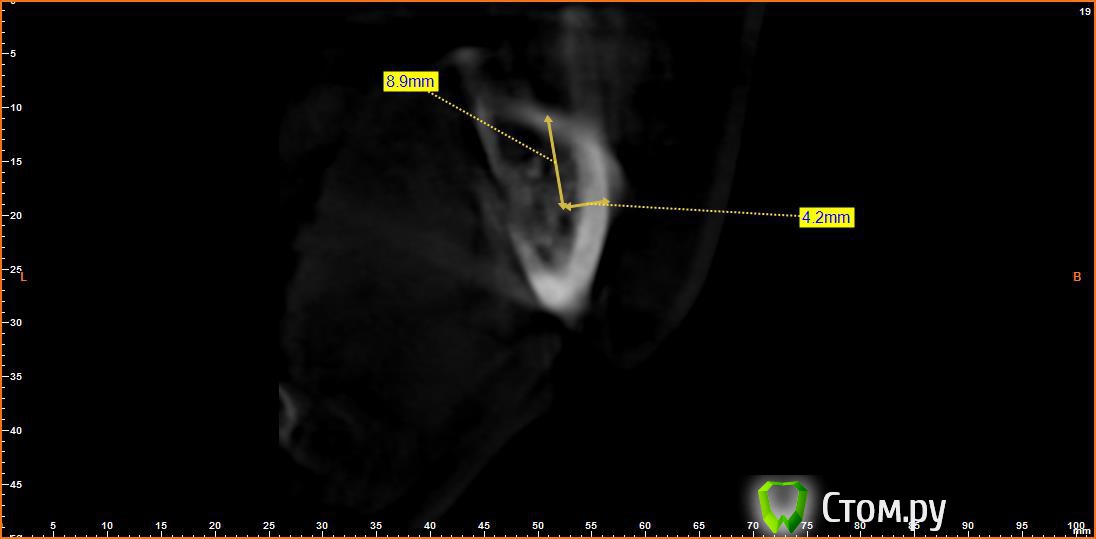

Bier Опубликовано 21 июня, 2014 Поделиться Опубликовано 21 июня, 2014 Выкладываю еще. Пошагово от 34-37темная точка достаточно высоко, это по моему не нерв, нерв ниже, я правильно понимаю? Ссылка на комментарий

Opimar Опубликовано 21 июня, 2014 Автор Поделиться Опубликовано 21 июня, 2014 темная точка достаточно высоко, это по моему не нерв, нерв ниже, я правильно понимаю?Да он ниже и язычнее. Провел от менталиса там еще запас есть. Ссылка на комментарий